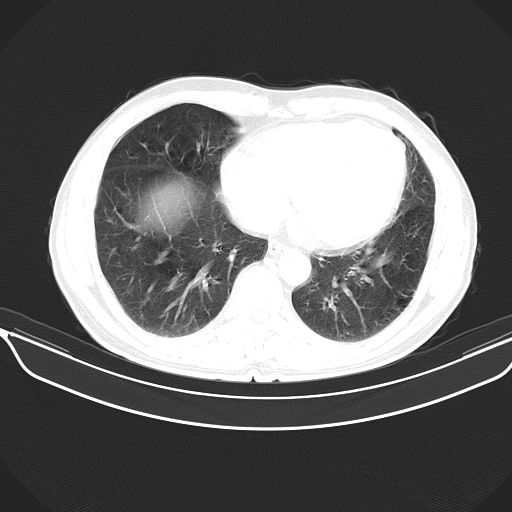

以下是引用心路寻觅在2010-3-1 10:23:00的发言:[br]1、考虑左肺上叶周围型肺癌[br]2、右上肺陈旧性病灶。[br][br][本贴已被 心路寻觅 于 2010-3-1 10:40:18 修改过]

以下是引用shuiyuan在2010-3-1 10:45:00的发言:[br]考虑左肺上叶中心型肺癌伴阻塞型炎症,邻近胸膜受侵。